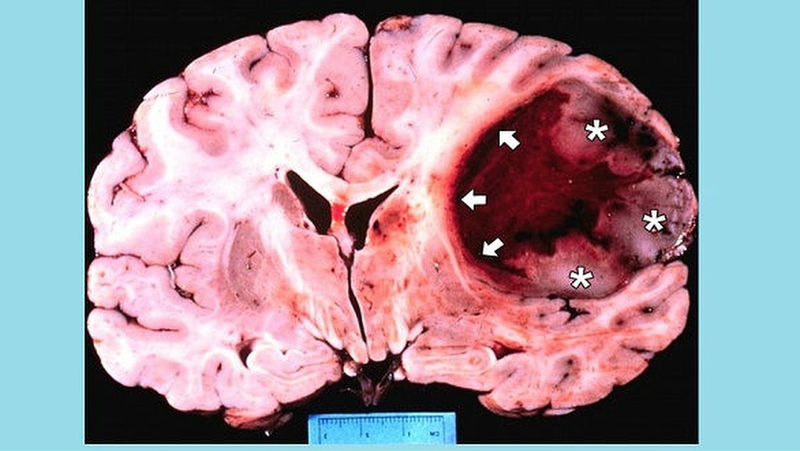

U bao thần kinh ngoại vi ác tính (MPNST) là một loại ung thư phát triển từ các dây thần kinh ngoại biên, là các dây thần kinh chạy từ tủy sống vào các bộ phận khác của cơ thể. Bệnh có thể xuất hiện ở bất kỳ vị trí nào trong cơ thể, nhưng thường xảy ra ở các mô sâu của thân, chân, cánh tay và mông. Bệnh có xu hướng gây đau, yếu và cảm giác ngứa ran ở vùng bị ảnh hưởng. U bao thần kinh ngoại vi ác tính được xem là một loại ung thư hung hăng, vì nó có khả năng mọc lại sau phẫu thuật hoặc lan rộng sang các cơ quan khác. Loại bệnh này rất hiếm gặp, chỉ chiếm khoảng 5% của tất cả các loại ung thư mô liên kết. Nó thường xảy ra ở người lớn, đặc biệt là những người có hội chứng neurofibromatosis loại 1 (NF1), một bệnh di truyền làm tăng nguy cơ phát triển các khối u thần kinh.